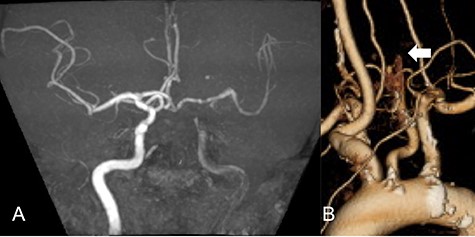

Repeated DWI images showed no significant expansion of the infarction, and complete recanalization of the left CCA was confirmed on MRA 2 weeks after initial onset (Fig. 2A). CTA revealed an irregular arterial wall and pseudo-lumen located in the CCA, extending to the bifurcation, suggesting an isolated left CCA dissection without the dissection extending to the aorta (Fig. 2B).

Two weeks after stroke onset, MRA revealed a complete recanalization of the left CCA (A). CTA also showed an irregular vessel wall and a pseudo-lumen located starting at the left CCA extending to the carotid bifurcation (B).